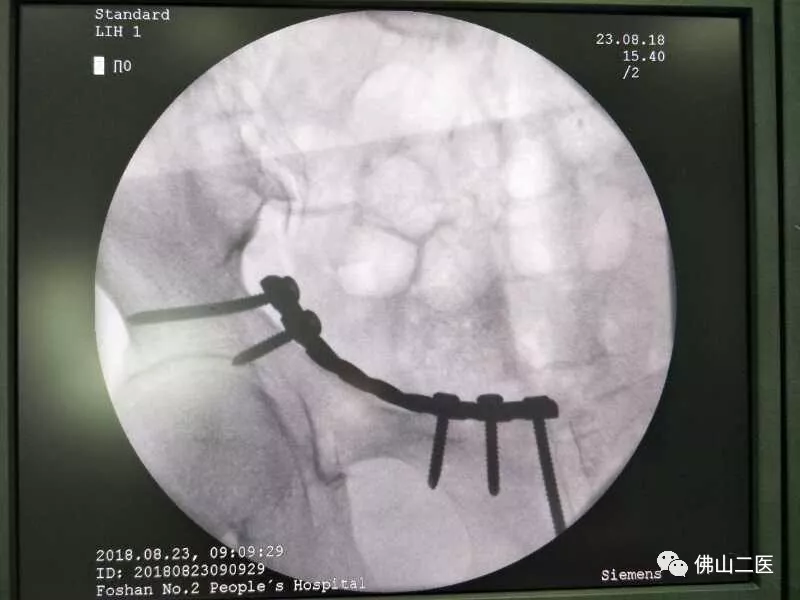

入院第3天,李女士被推进了手术室,邱华耀主刀,带领团队为她行改良Stoppa入路骨盆骨折手术。

以往的骨盆骨折手术,耗时长、出血多,考验着麻醉医生的麻醉水平及手术室护士的配合程度,但参与此次手术的麻醉医生及护士纷纷坦言“担心过度了!”。就本例患者而言,由于邱华耀经验丰富,手术操作娴熟,手术耗时仅用了45分钟,出血量仅有100毫升!患者术中及术后的生命体征十分平稳,而且因为术中出血少,也不用术后输血。